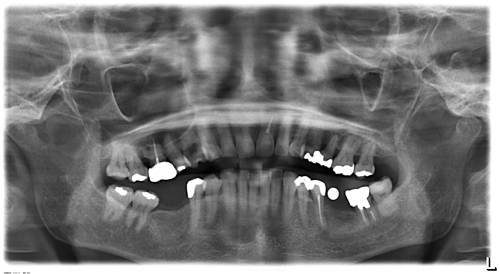

術前のレントゲン写真です

歯周病や虫歯など細菌感染による疾病は原則的に術前に治していますので、悪い歯を取った後のように腫れることは少ないです。